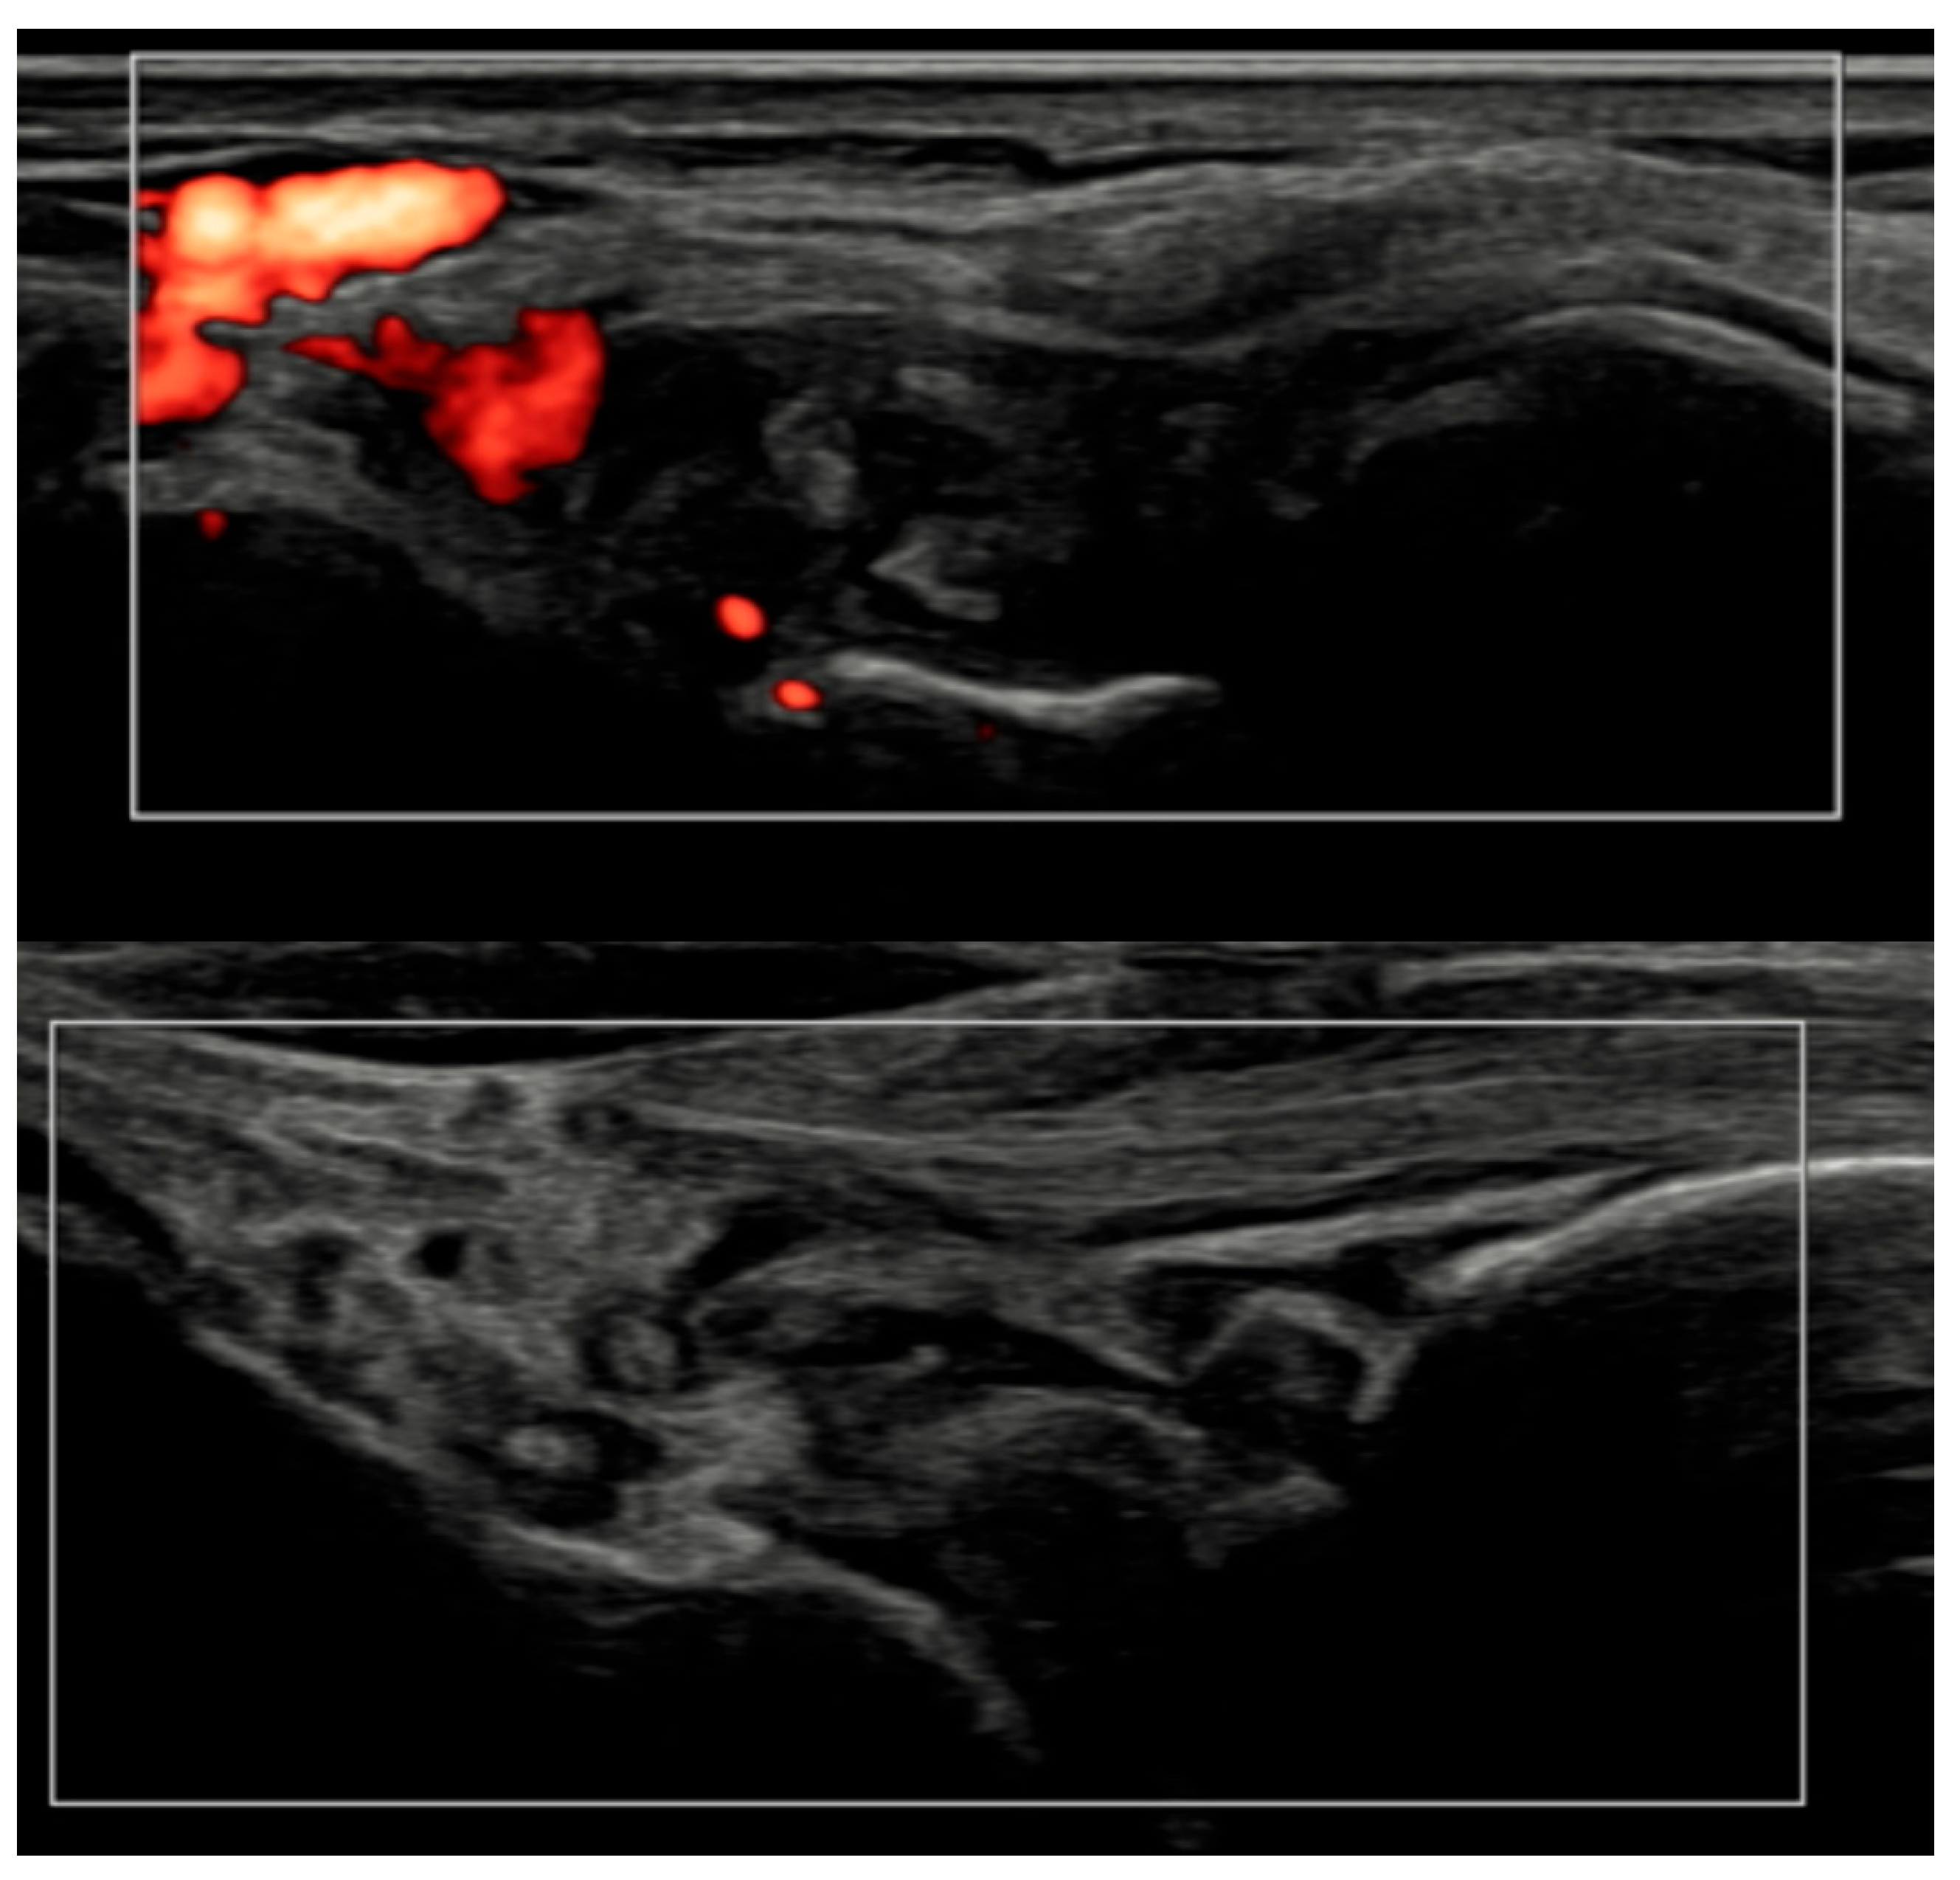

Figure 6.

Longitudinal ultrasound comparison of the wrist joint at baseline (T0, top) showing synovial hypertrophy (grade 2) with intra-articular power Doppler signal (PD grade 2), corresponding to a combined EULAR–OMERACT synovitis grade = 2 (joint-level), and at 6 months (T6, bottom), demonstrating near-complete resolution of synovial hypertrophy and power Doppler signal, with a joint-level EULAR–OMERACT synovitis grade = 0.